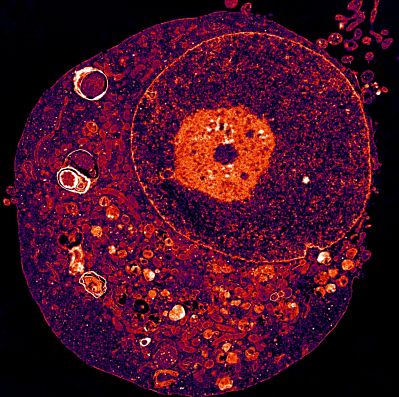

Par une approche d’imagerie cellulaire, les chercheur.e.s ont également remarqué que le blocage de l’activité du gène - ou la réduction de son expression - provoquait dans les GSCs une augmentation incontrôlée et fatale en lysosomes, les structures intracellulaires qui agissent normalement comme des stations de recyclage.

Crédit photo : © Julie Gavard